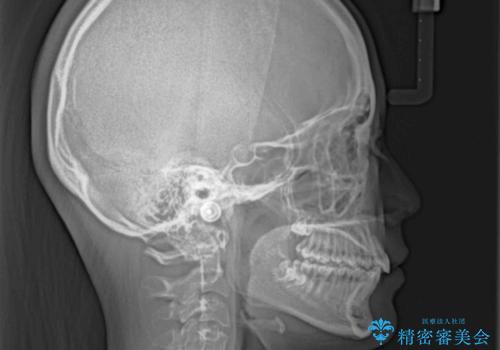

奥歯の咬み合わせを見ると、上顎が下顎に対して相対的に前方にありました。

深い咬み合わせを改善するためには、上顎臼歯を後方に移動させつつ、下顎の小臼歯を直立させる必要があります。

ワイヤー装置と補助装置を有効に活用し、さらには高校生ということもあり、1年9か月で狙い通りの仕上がりを達成することができました。